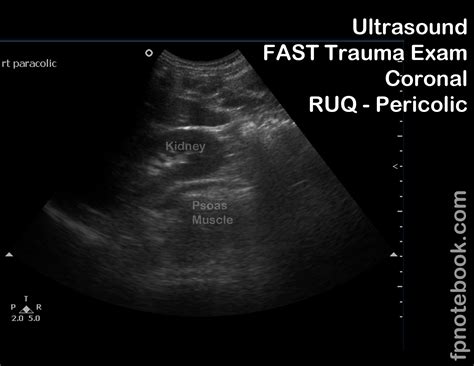

• EFAST (Extended Focused Assessment with Sonography for Trauma): This is a comprehensive ultrasound examination used to evaluate patients with trauma. It includes views of the heart, lungs, abdomen, and pelvis to detect fluid collections, pneumothorax, and other injuries.

• Focused Abdominal Ultrasound: This evaluates the abdomen for free fluid, organomegaly, and other abnormalities.

• Trauma Assessment: In trauma patients, the Fast Exam Ultrasound helps identify internal injuries, such as hemoperitoneum, hemothorax, and pericardial effusion.

• Abdominal Evaluation: It helps identify free fluid in the abdomen, organomegaly, and other abnormalities.